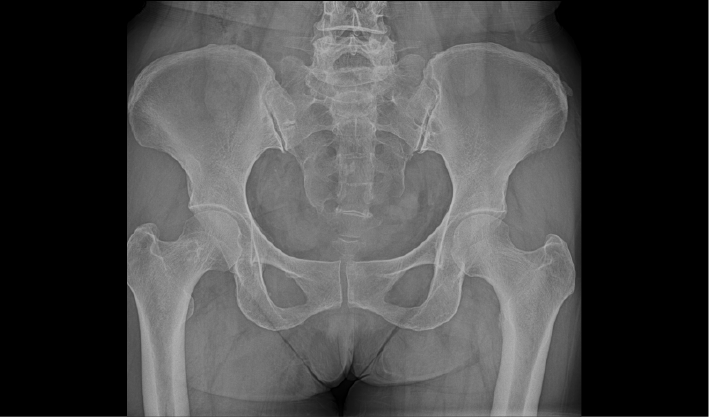

常规DR摄影检查,如:胸片位,腹部位,四肢位等。

成熟优秀的动态成像技术,在透视下实时观察内部器官运动状态,并可快速高清点片,动静结合,多视角精准观察病灶。